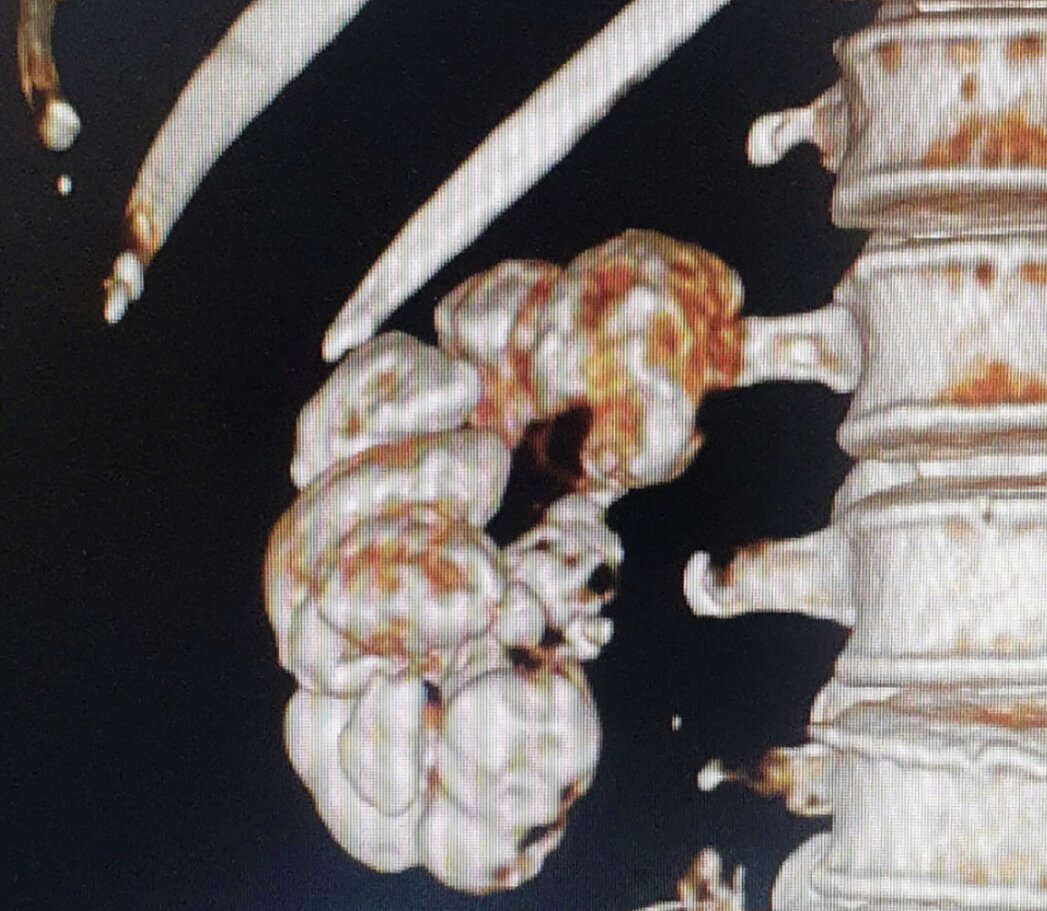

ThS.BS Cao Vĩnh Duy, khoa Tiết niệu – Trung tâm Tiết niệu, Thận học, Nam khoa, Bệnh viện Đa khoa Tâm Anh TP.HCM cho biết, hình ảnh CT scan cho thấy toàn bộ thận phải bị vôi hóa, trắng xóa hay còn gọi “thận hoá đá”, không bắt thuốc cản quang. Đây là dấu hiệu cho thấy thận đã mất hoàn toàn chức năng.

Bác sĩ nghi ngờ bệnh nhân mắc lao thận mạn tính, khiến thận mất chức năng. Bác sĩ đánh giá giải pháp điều trị tối ưu là phẫu thuật cắt bỏ toàn bộ thận phải để loại bỏ ổ bệnh, đồng thời gửi mẫu đi giải phẫu bệnh nhằm xác định chính xác nguyên nhân.

Bệnh nhân được chỉ định phẫu thuật nội soi cắt bên thận phải đã “hoá đá”. Trong quá trình mổ, ê-kíp phát hiện quả thận có hình dạng xù xì, chứa mủ vàng, động mạch thận teo nhỏ, hoàn toàn không còn khả năng cung cấp máu nuôi.

Quả thận được lấy ra đem đi giải phẫu bệnh. Kết quả cho thấy mô thận bị hoại tử bã đậu, đây là đặc trưng của bệnh lao thận.